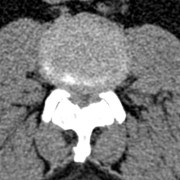

- anomalies rachidiennes : canal étroit, spondylolisthésis

attention, il existe souvent chez l’adulte un canal lombaire étroit associé,

parfois une lyse isthmique ; cette dernière ne nécessite pas forcément de prise en charge spécifique. la laminectomie doit être précautionneuse car le rachis lombaire bas contient la moelle, et non la queue de cheval.